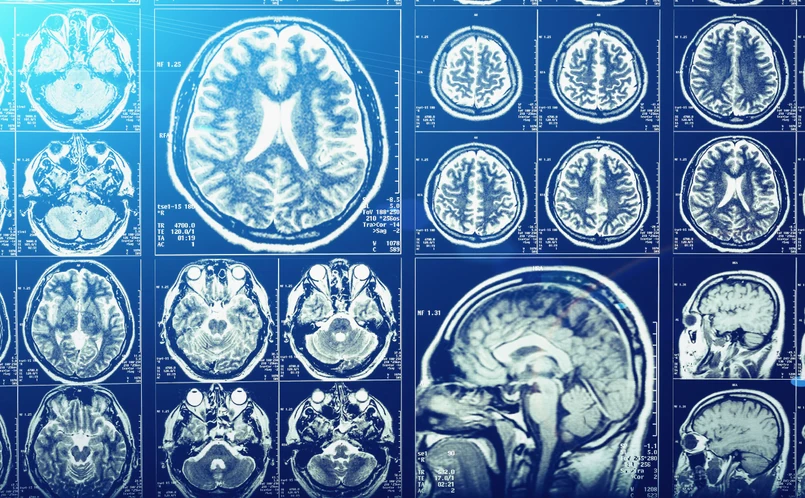

Choć wydawać by się mogło, że anatomia człowieka już od dawna jest dobrze poznana, to bywa, że naukowcy odkryją jakąś nową, nieznaną wcześniej strukturę w ludzkim ciele. Tak było z setkami niewielkich kanalików w czaszce odkrytymi jakiś czas temu przez zespół z Massachusetts General Hospital (MGH).

W 2018 roku naukowcy z MGH zauważyli, że komórki reagujące na infekcje i urazy mózgu pochodzą ze szpiku w czaszce i że przechodzą one właśnie przez wspomniane kanaliki, które łączą szpik czaszki z obszarem wokół opon mózgowych.

W najnowszej pracy (https://www.nature.com/articles/s41593-022-01060-2) badacze pokazali natomiast, że oprócz przepuszczania komórek odpornościowych ze szpiku do mózgu, kanaliki umożliwiają wnikanie do szpiku płynu mózgowo-rdzeniowego.